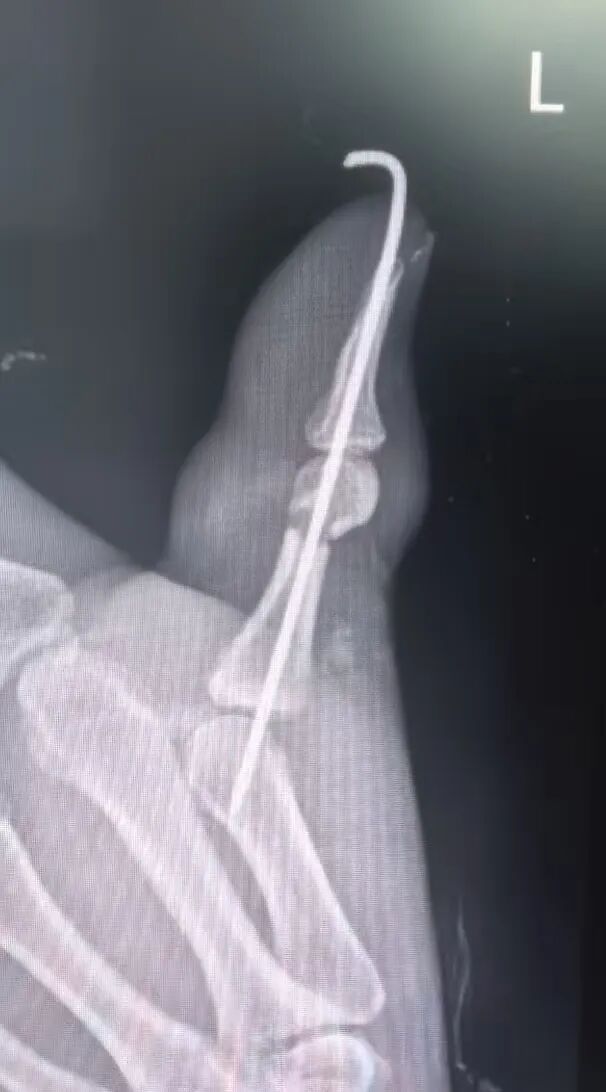

在剧痛中煎熬度过4天后,终于达到非洲,李先生第一时间被送往当地医院,在环境简陋的“手术室”完成了“左手拇指清创+指骨骨折内固定”。

向炜医生在晨交班上,结合患者的病史及相关辅助检查汇报了病情:“目前主要考虑左手拇指骨折术后感染,皮肤软组织情况差,很可能骨髓也已感染。若不及时控制,存在截指可能。”

向炜医生回忆术中情况也满是挑战:骨折固定位置奇特,伤口缝线粗大无比!此外不仅伤口感染重,坏死组织多,而且屈伸肌腱未修复,屈肌腱回缩未见,伸肌腱砸伤毁损;桡侧血管神经未修复;整个拇指仅靠尺侧指动脉及少许皮肤软组织相连,危在旦夕!